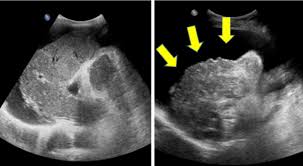

10.복수 및 말초 부종

복수의 발생

간수치가 높아지면 복수가 발생할 수 있습니다. 이는 간 기능 저하로 인해 복강 내에 체액이 축적되는 현상으로, 복부가 팽창하고 불편감을 초래할 수 있습니다. 복수는 간경변 환자에서 흔히 나타나는 증상입니다.